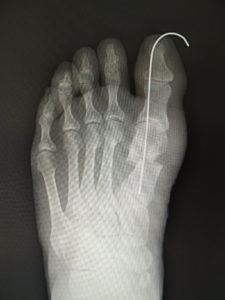

手術前 手術後4年

最近では、原則として固定ワイヤーは経皮的の一本のみとし、ワイヤーの先端は皮膚の外に出ているので、抜く時(術後3週間目)の患者さんの負担はほぼありません。こうすることによるデメリットはなく、むしろ術後成績は良くなっています。

(図6)

手術前 手術後

(図7)

真田理事長による手術の様子。外反母趾|症例 (左から 手術前、手術後、ワイヤ抜去後)